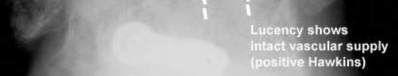

A 25-year-old female is involved in a motor vehicle collision. She presents with the isolated injury seen in Figures A through D. Her leg is swollen but her skin is intact. She has no clinical signs of compartment syndrome. Which of the following treatment options will allow for maintenance of fracture alignment and minimize the risk of soft tissue complications?

The patient presents with a closed distal third metaphyseal-diaphyseal distal tibia fracture with simple intra-articular extension. Immediate intramedullary nailing along with percutaneous fixation of the articular component provides appropriate restoration of length, rotation and alignment and minimizes the risk of wound complication.

Displaced distal third tibia fractures may be associated with simple intraarticular extension. Operative treatment of intra-articular distal tibia fractures has historically been performed with open reduction and internal fixation. Early open reduction and plate fixation of pilon fractures has been associated with high rates of infection and wound complication. In select patterns with simple articular extension, percutaneous screw fixation and medullary nailing may provide appropriate reduction with minimal soft-tissue risk.

Figures A and B demonstrate a distal third tibial shaft fracture with simple intra-articular extension. The axial and coronal CT cuts in Figures C and D further clarify the articular injury. Illustrations A and B demonstrate a comminuted distal third tibial fracture with simple intra-articular extension. Illustrations C and D are fluoroscopic images of the same injury after intramedullary nailing and percutaneous fixation of the articular component.